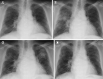

Figure 1.

Abnormal shadow in the right lower lung field was observed in the first chest X-ray (1a). The shadow had migrated to the right upper lung on Day 868 (1b). The shadow had migrated in the left upper lung on Day 986 (1c). The shadow had almost disappeared on Day 1,048 (1d).